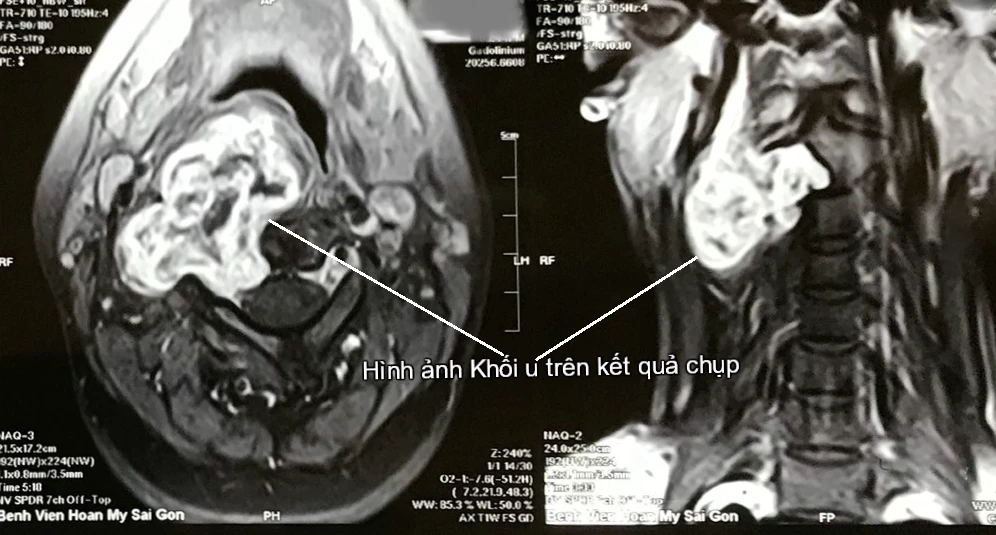

Tại đây, các bác sĩ đã chụp MRI và cho kết quả khối u của chị là u bao dây thần kinh C2-C3 bên phải, xâm lấn thành họng bên phải. Lúc này, khối u có đường kính 6 cm.

Hình ảnh khối u trên kết quả chụp. Ảnh: BV

Khối u có vỏ bao rõ ràng, hình cầu hoặc hình bầu dục, mật độ thay đổi dạng nang mềm hoặc cứng chắc.

Điều trị khối u bao dây thần kinh chủ yếu là phẫu thuật, tiên lượng sau mổ tốt là do các khối u này thường có lớp vỏ bao rõ ràng. Tuy nhiên, vị trí khối u lại thường ở sâu, sát nền sọ, sát với các mạch máu lớn và thần kinh khác nên việc chọn đường vào khối u phải rất cẩn thận.